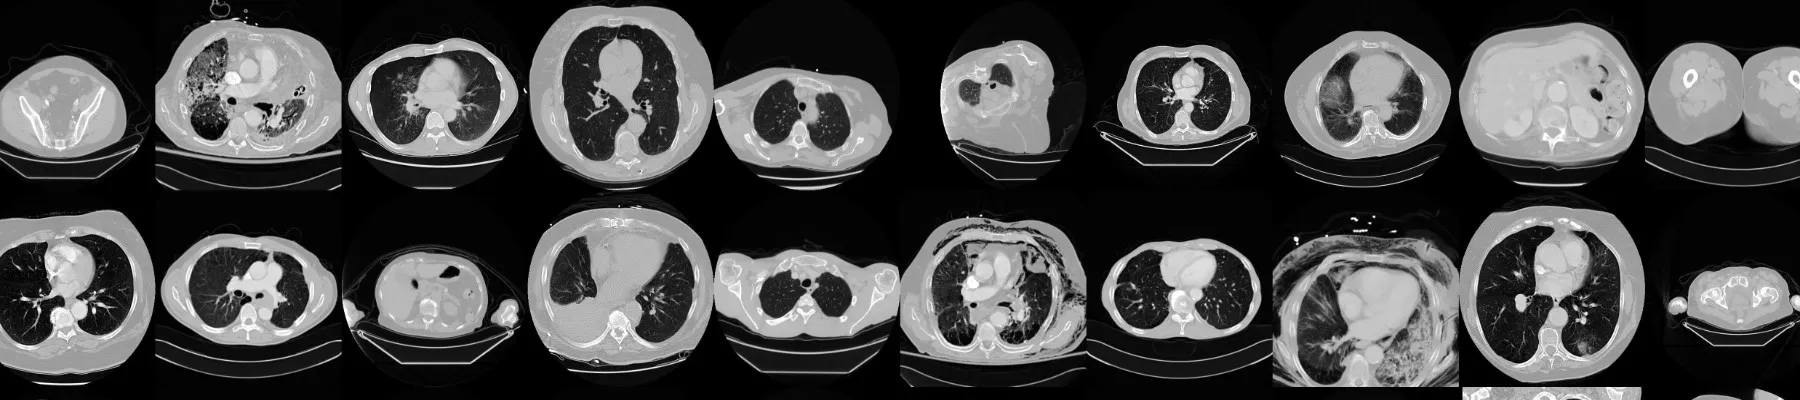

AI-Based Medical Image Classification: Deep learning is now a standard tool for assisting radiologists. Building a model to detect pneumonia from X-rays or lesions from MRIs teaches the importance of model sensitivity, specificity, and the ethical implications of diagnostic AI.

Semantic Segmentation with U-Net: Unlike classification, segmentation requires pixel-level precision. Implementing a U-Net architecture to isolate tumors or organs in medical scans demonstrates a developer’s ability to handle high-stakes, grayscale data with complex boundaries.